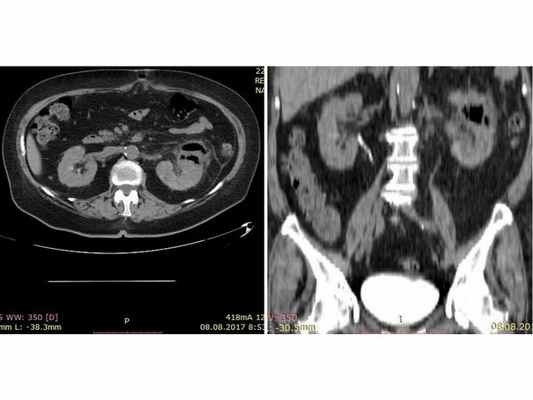

Считает себя больной с мая 2017 года, когда впервые возникли болевые ощущения в левой половине живота и повышение температуры до 39,0°C. Проходила лечение у терапевта и хирурга ЦРБ, но динамика была отрицательной: интенсивность болей в животе нарастала, и к июлю месяцу они стали нестерпимыми, приобрели распирающий характер, что заставило пациентку настоять на оперативном лечении, так как у неё было желание "разорвать живот, чтобы выпустить боль". 17 июня госпитализирована в хирургическое отделении ЦРБ. На следующий день пациентке проведено УЗИ органов брюшной полости и почек: выявлены косвенные признаки патологии сигмовидной кишки и слабовыраженные диффузные изменения паренхимы почек. 19 июня выполнена диагностическая лапаротомия: патологии органов брюшной полости не выявлено. 24 июня пациентка переведена в отделение терапии ЦРБ. Проводилась антибактериальная (цефтриаксон, левофлоксацин, моксифлоксацин, метронидазол) и инфузионная терапия, но без стойкого эффекта — боли в пояснице слева сохранялись, температура повышалась до 38,0°C. 7 августа выполнено УЗИ почек: визуализируются умеренные диффузные изменения паренхимы левой почки, а также объёмное образование левой почки неоднородного характера с пузырьками газа, которое распространяется на околопочечную клетчатку, размерами 50*40*40 мм (вероятно, абсцесс). Для дальнейшего лечения 8 августа переведена в урологическое отделение города.

Результат мультиспиральной КТ: видны изменения левой почки, характерные для эмфизематозного пиелонефрита, функция левой почки отсутствует